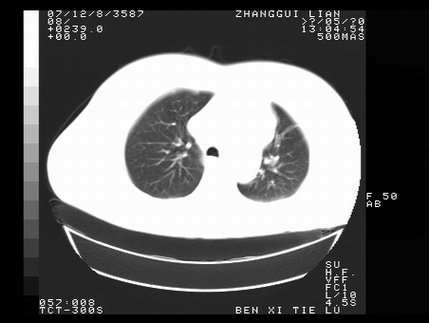

标题: CT10817:女,46,胸疼,无其他病史 [打印本页]

标题: CT10817:女,46,胸疼,无其他病史

左侧上纵隔旁团块影,部分植入纵隔,与纵隔界限不清,另:左肺门明显见团块,气管隆突前方见肿大淋巴结。考虑:左上肺纵隔型肺癌伴左肺门及纵隔淋巴结转移!

首先考虑左侧中央型肺癌伴阻塞性肺炎、纵隔内、弓旁淋巴结转移可能性大(纵隔窗调的欠佳)

1左上肺中心型肺癌伴左肺上叶不张2主动脉弓旁淋巴结转移3左下肺炎症

1 左侧中央型肺癌伴阻塞性肺炎 2 左肺门及纵隔淋巴结转移!3两侧胸腔及心包积液.

左侧胸廓塌陷,纵隔向左侧移位,左上肺不张。